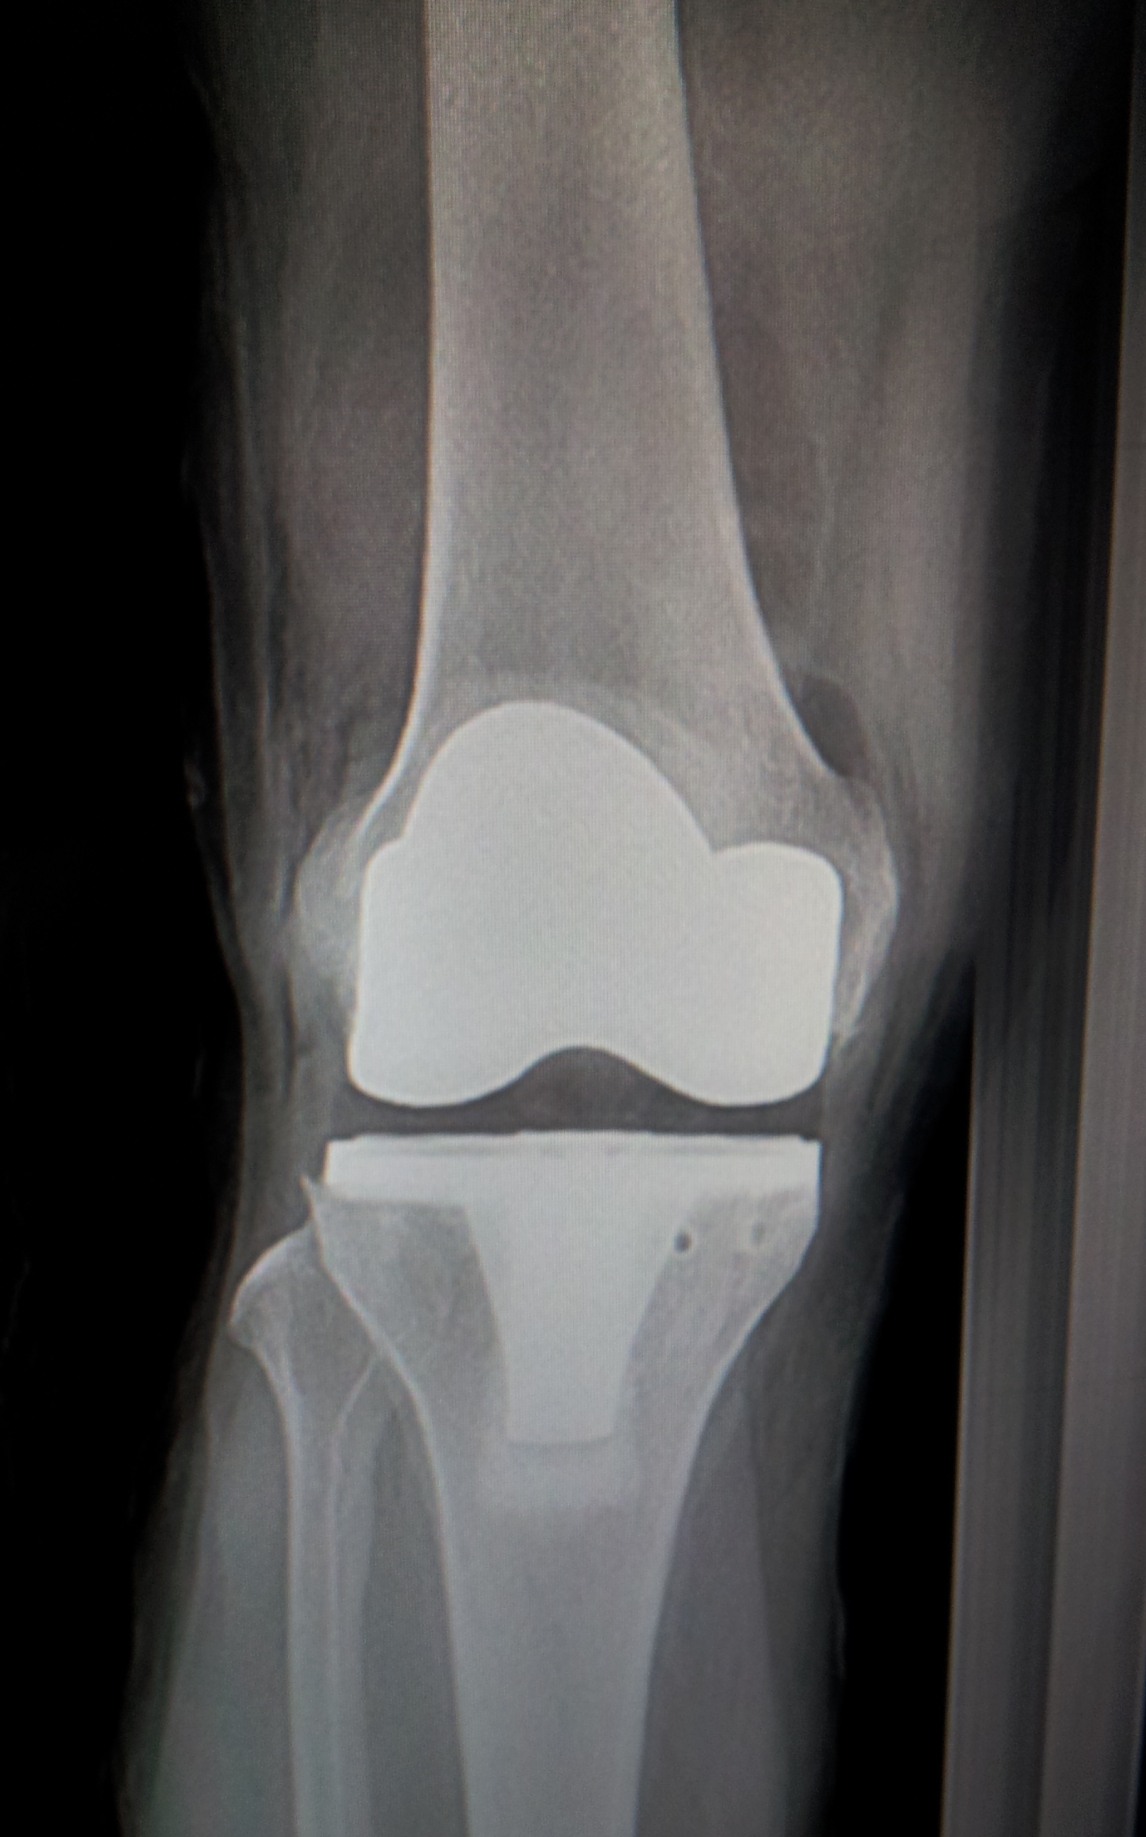

人工膝关节置换术简介

膝关节置换在上个世纪70和80年代开始广泛应用于临床,目前已被认为是终末期膝关节骨性关节炎的有效治疗手段。

TKR的主要临床指征是膝关节骨性关节炎,这大约占所有手术量的94-97%。导致膝关节骨性关节炎病变的原因复杂,是患者本身体质状况与膝关节所受机械力量共同作用的结果。这些相关因素包括骨密度、骨形态、半月板退变、性别、性激素、以及创伤等,但最主要的危险因素是年龄和肥胖。目前通常公认膝关节终末期骨性关节炎以及持续性严重疼痛是TKR的主要手术指征。罹患上述病变的患者无法通过关节镜手术解决相关问题。据国内外资料显示,人工全膝关节置换术后约有90%的关节假体可有效使用20年左右。

关节置换是外科领域最成功的创新范例之一,它极大地提高了终末期关节炎患者的生存质量,我科已成功开展膝关节置换术多年,疗效满意。